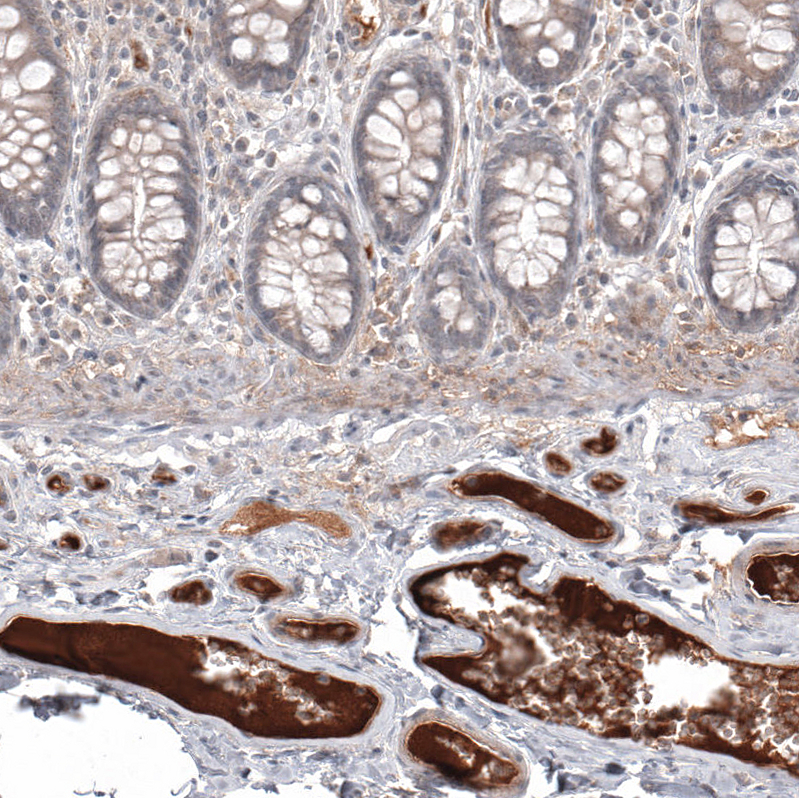

Immunohistochemical staining of human colon shows strong positivity in plasma.